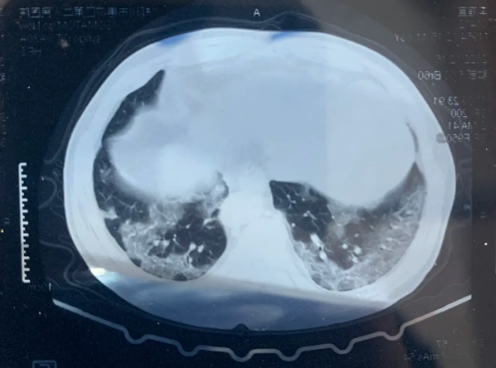

许多病原引起的症状很轻,属于自限性疾病,部分病原仅引起上呼吸道症状(比如:咽喉痛、流鼻涕等)。而有些病原会引起较为严重的症状,包括支气管炎、重症肺炎和急性呼吸窘迫综合征等,如果不及时干预,甚至可能发生肺水肿、白肺等严重并发症。